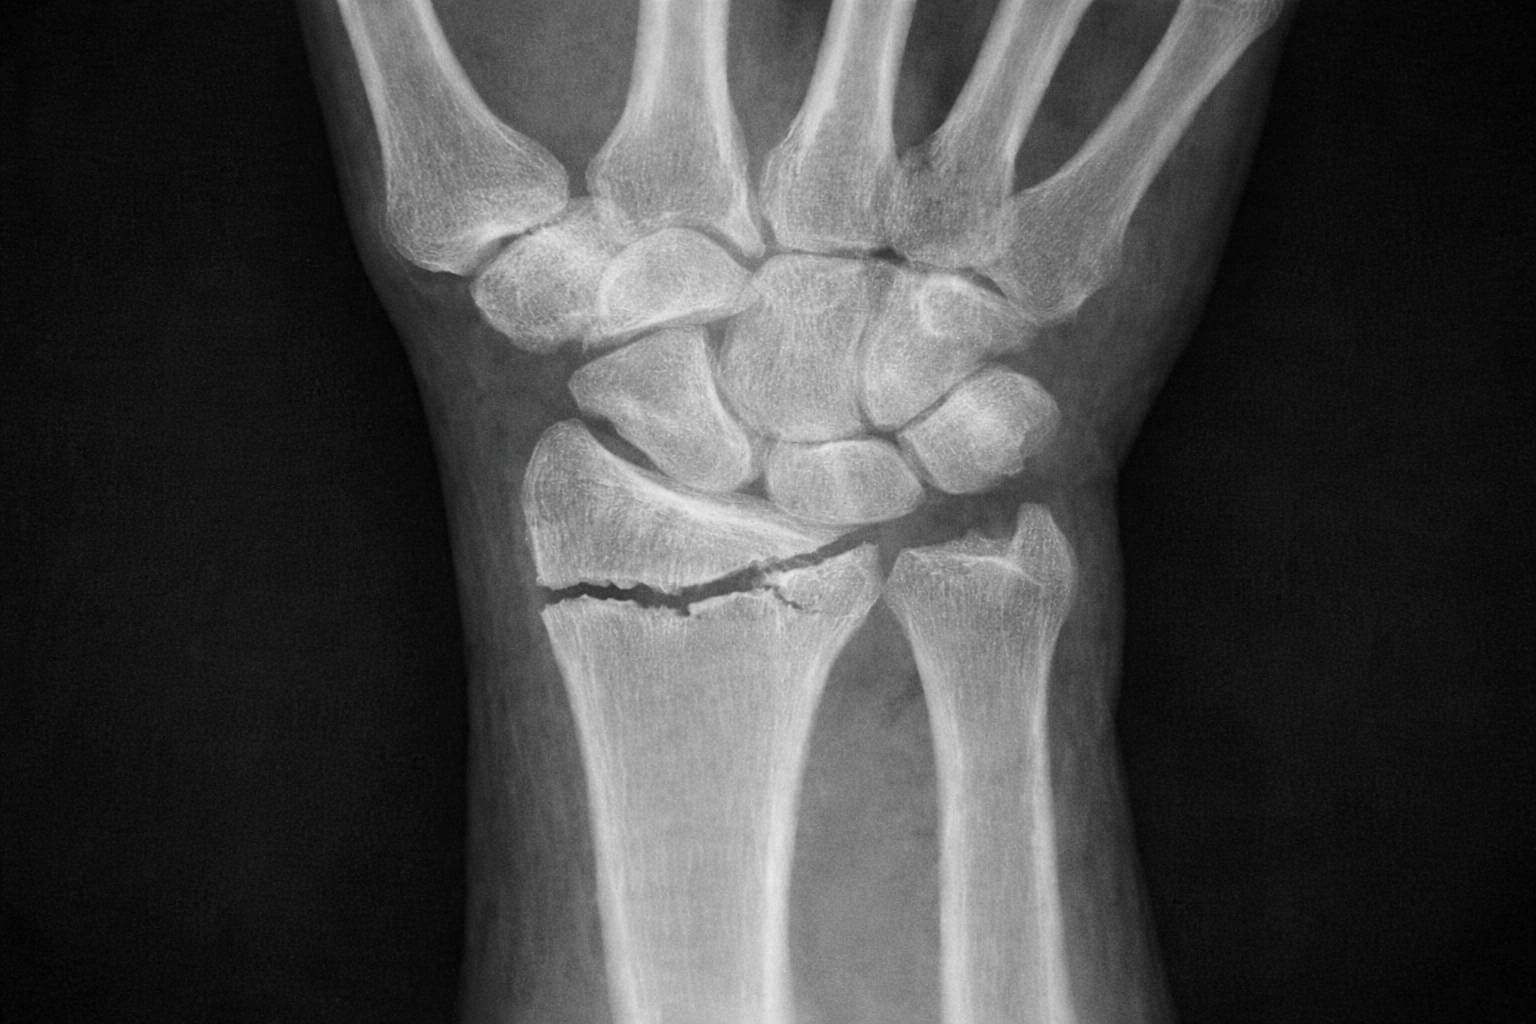

Scopri le terapie più efficaci per gestire il dolore intenso e recuperare la forza nella presa in seguito a una frattura del radio o dell’ulna.